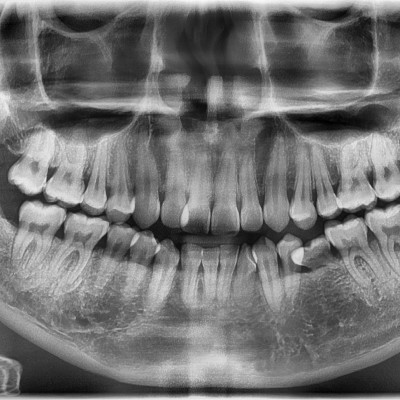

#28,38 사랑니 발치 #28,38 사랑니 발치 구강 외과 전문의가 당일 발치했습니다. ------------------------..

#18,28,48 사랑니 발치 #18,28,48 사랑니 발치 구강 외과 전문의가 당일 발치했습니다. ---------------------..

#18사랑니 발치 + #19 과잉치발치 #18사랑니 발치 + #19 과잉치발치 구강 외과 전문의가 당일 발치했습니다. ---------------..

#28,38 사랑니 발치 #28,38 사랑니 발치 구강 외과 전문의가 당일 발치했습니다. --------------------------..

#28,38,48 사랑니 발치 #28,38,48 사랑니 발치 구강 외과 전문의가 당일 발치했습니다. -----------------------..

#38,48 사랑니 발치 #38,48 사랑니 발치 구강 외과 전문의가 당일 발치했습니다. --------------------------..

#18,28,38,48 사랑니 발치 #18,28,38,48 사랑니 발치 구강 외과 전문의가 당일 발치했습니다. --------------------..

#28 사랑니 발치 #28 사랑니 발치 구강 외과 전문의가 당일 발치했습니다. -----------------------------..

#38,48 사랑니 발치 구강 외과 전문의가 당일 발치했습니다. #38,48 사랑니 발치 구강 외과 전문의가 당일 발치했습니다. --------------------------..

#18,48 사랑니 발치 #18,48 사랑니 발치 구강 외과 전문의가 당일 발치했습니다. --------------------------..

#38 사랑니 발치 #38 사랑니 발치 구강 외과 전문의가 당일 발치했습니다. ------------------------------..